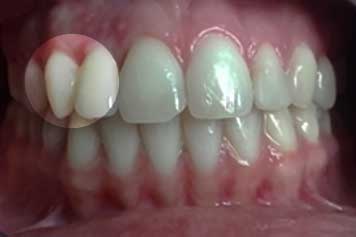

Etapa 2

Planificación quirúrgica del caso, y colocación de implante que repone incisivo lateral.

Implante por Agenesia Dentaria Implante por Agenesia Dentaria